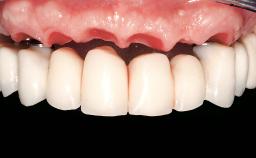

ITI Curriculum FL: Patient Assessment Case 7

Example intended for case-based discussion regarding patient assessment, diagnosis and determination of risk and complexity.

| Case Type | Short Space |

| Jaw | Maxilla |

| Area | Posterior |

| # of Teeth | 2 |